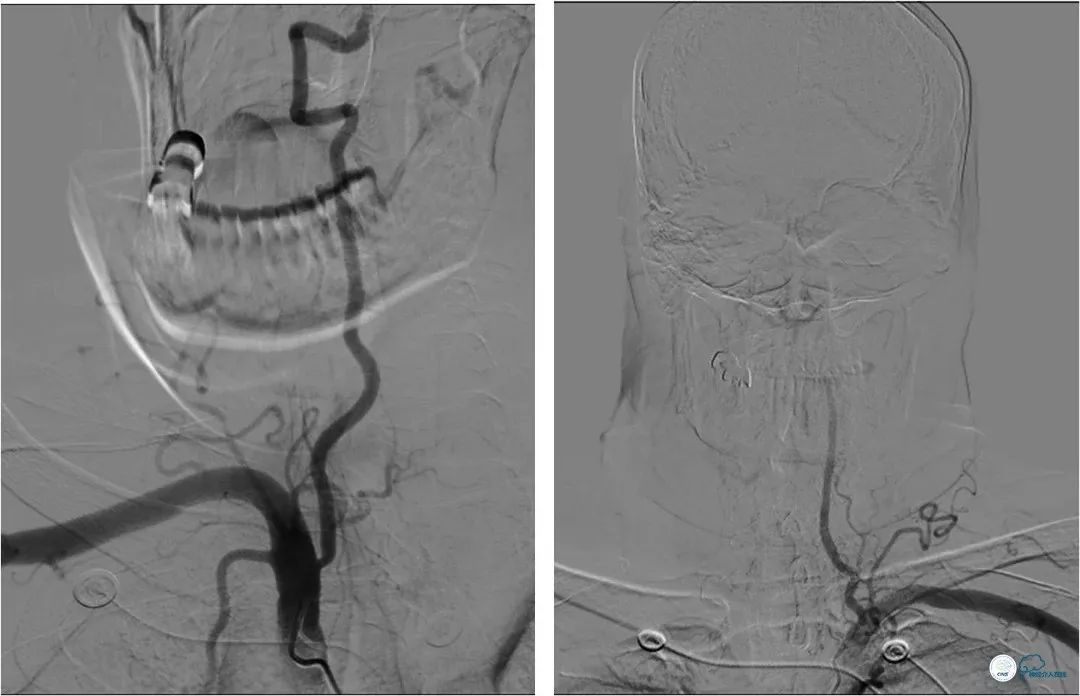

患者,男,72岁。主因“反复头晕3年”入院。患者3年前突发短暂头晕,无其他伴随症状,就诊于当地医院,行CTA提示:双椎动脉V4段-基底动脉交界区狭窄。3年来症状反复发作,多次行颅内动脉血管成像,显示病变程度逐渐加重(图1)。

DSA提示:左椎动脉开口迂曲,右椎动脉开口中度狭窄(图5)。双椎动脉V4段与基底动脉交界处重度狭窄,左侧狭窄程度更重(图6,7)。